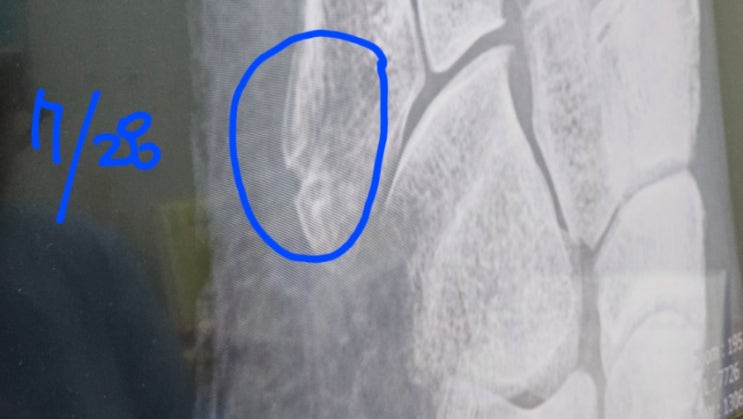

발등골절 비수술 제5중족골 기저부골절 6주차

운동 나갔다가 비포장 길 걸어가다가 움푹 파여 있는길을 못보고 빠지면서 발이 접질렸다. 그곳에 또 돌맹...

발등골절 제5중족골 기저부골절 비수술 4주차 5주차

발등골절 제5중족골 기저부골절 비수술 3주차 꽉차고 4주차 시작(7.14)일인 월요일에 병원가서 사진 찍었습...